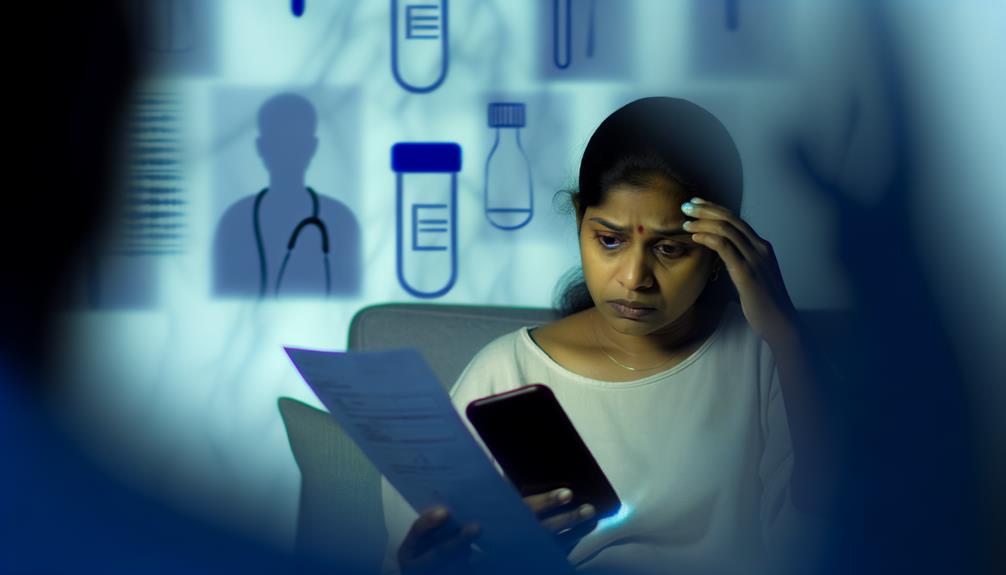

Mythes courants sur les tests de dépistage des ITSS

Découvrez les mythes courants autour des tests de dépistage des IST et pourquoi ils pourraient mettre votre santé en danger.

Faux positifs et faux négatifs dans les tests ITSS : Que faire ?

Informez-vous sur les faux positifs et les faux négatifs dans les tests MST et découvrez les étapes à suivre pour gérer l'incertitude.